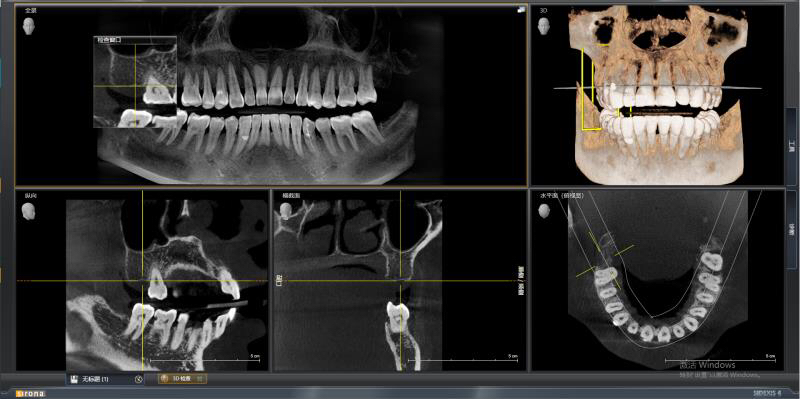

今天给大家分享的病例是一位中年女性,17缺失,由于长时间未修复,47伸长,留给17修复的空间不足。

老卢给她的治疗方案是:17种植修复,47根管治疗后截冠、高嵌体修复。这样可以最大限度的增加患者的咀嚼效率。